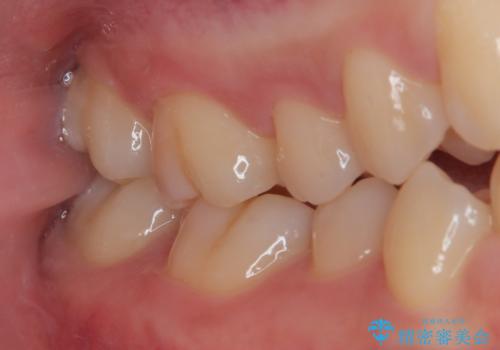

ゴールドインレー(PGAインレー)はセラミックインレーと比べ、歯の切削量が少なく、適合性が著しくいいことが特徴です。上顎の奥歯は見えないので機能面でゴールドインレー、ゴールドクラウンはおすすめです。